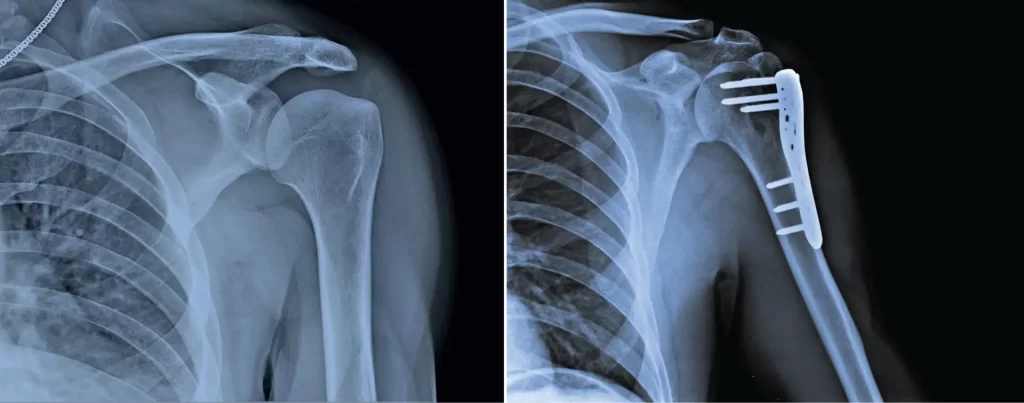

Below is a brief overview of how some of the more common geriatric fractures are managed, and what you can expect during these treatments.